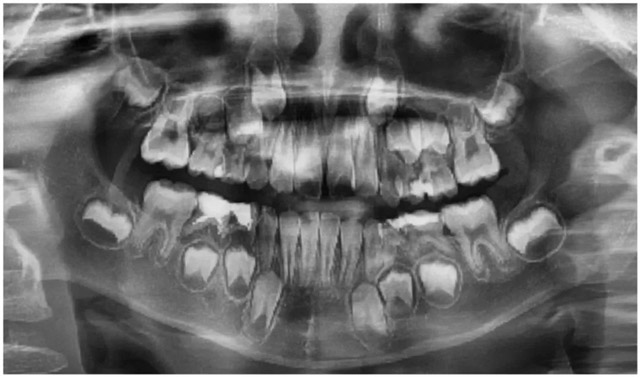

到院后,石佳桐医生为莉莉安排了全面检查,根据全景片、CBCT、口扫检查结果显示,莉莉存在牙弓狭窄、门牙唇倾、深覆盖等问题,这些问题已经影响到了她的正常咬合,需要进行早期矫正干预。

牙弓狭窄、牙列拥挤、门牙唇倾、深覆盖深覆合。

莉莉口腔全景片(替牙期,牙齿拥挤)